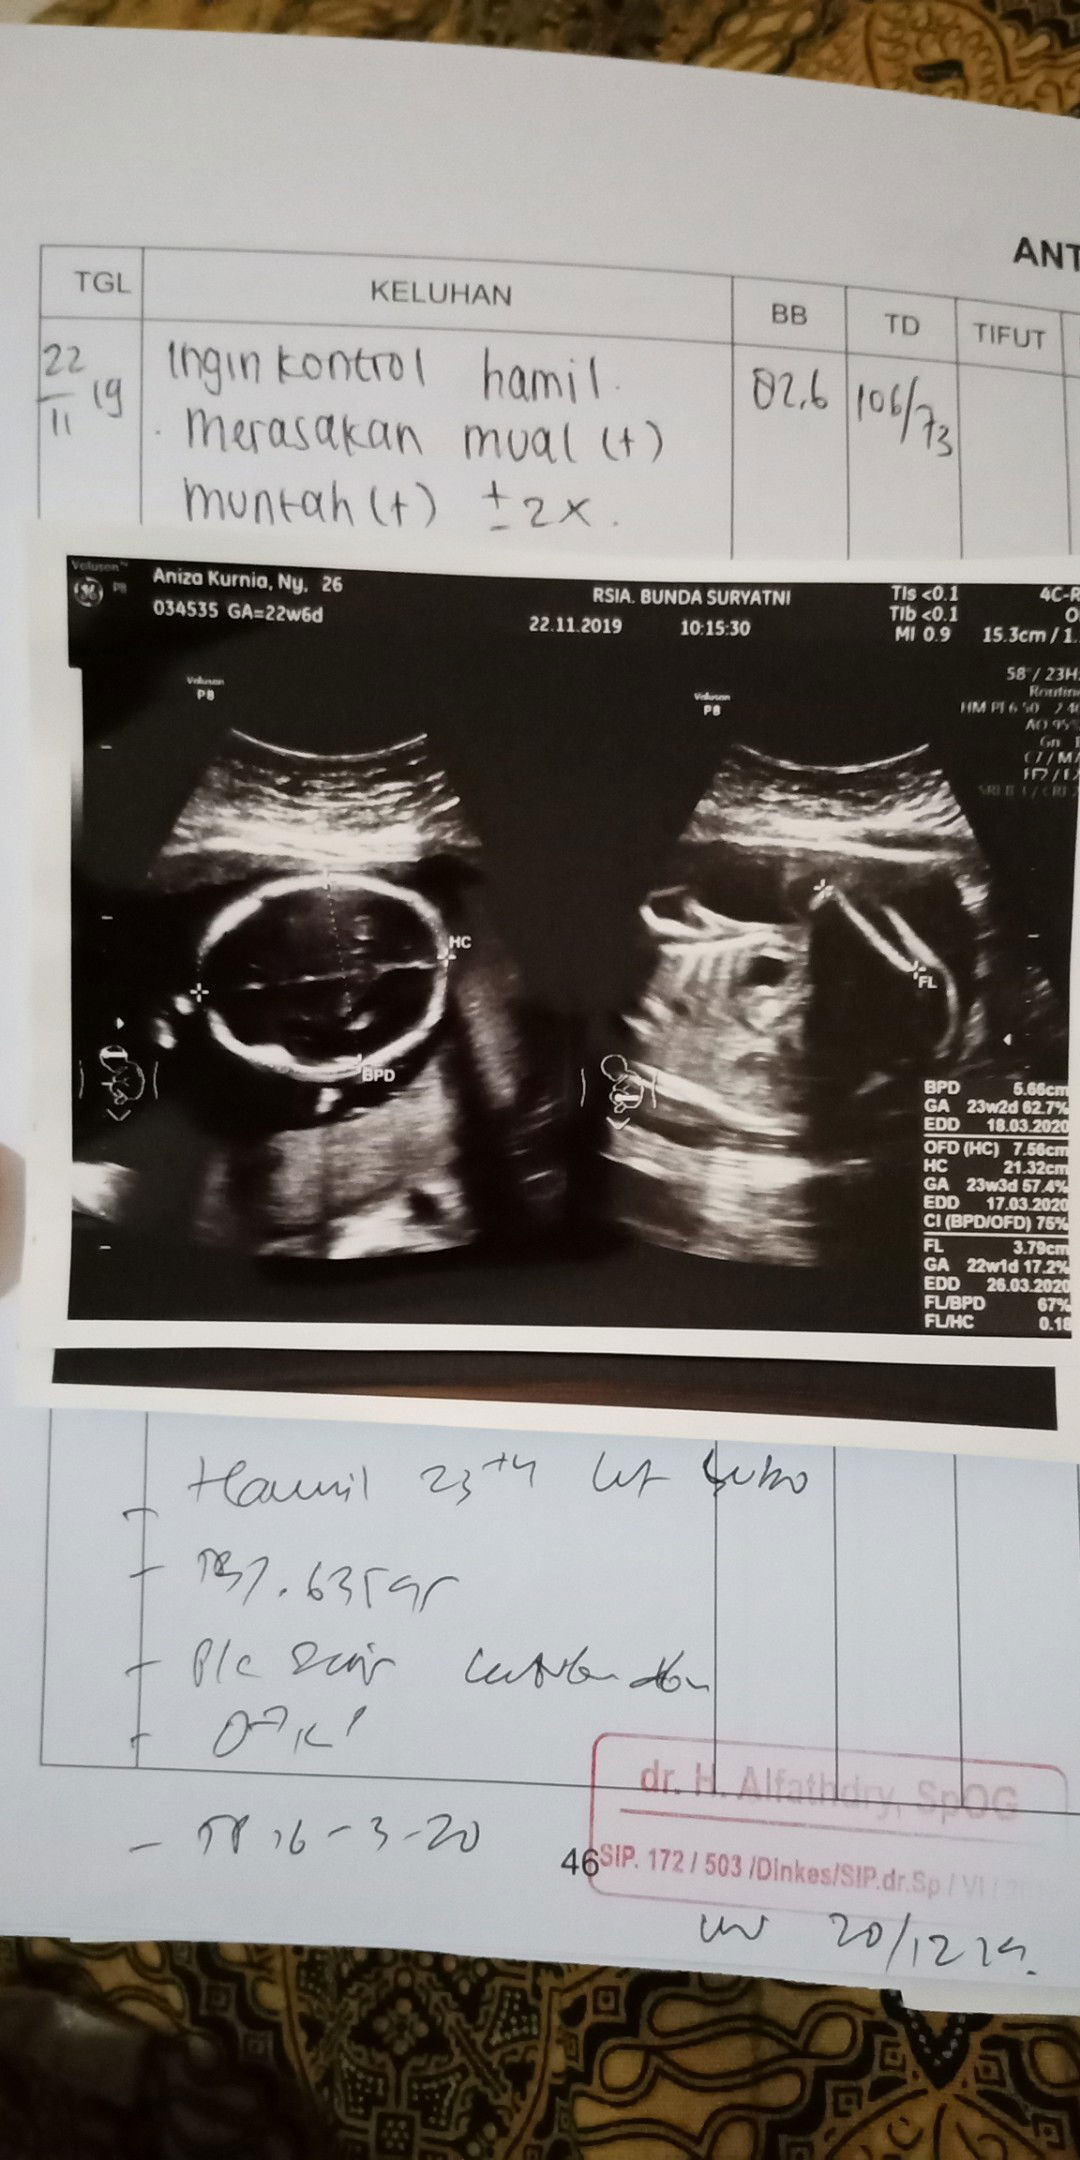

22 Nov 2019 Kontrol bulanan kehamilan Di 24 week ini aku merasakan Mual Dan muntah BB ku Naik 1Kg dari Bulan sebelumnya Dan janin sekarang 635g yang sebelumnya 323g Tensi Masih rendah 106/73 Posisi janin sungsang,kepala di atas Dan disarankan banyak jalan agar kepala janin di bawah lagi. Disini obat cal 95 Dan promavit Di stop Oleh dokter Karna mungkin aku ngga bisa minum obat pil Dan Malah Jadi Mual Dan muntah Setiap malam, Jadi di Ganti Elkana CL yang syrup untuk ibu hamil. Oiya moms Selama Hamil aku ngga Nafsu Sama sekali Untuk ngerujak - Padahal sebelum Hamil aku Suka banget ngerujak Untuk minum Susu Hamil Awalnya Bulan pertama aku minum Prenagen coklat tapi Jadi Mual Dan Enek. Akhirnya aku Ganti greenfileds strawberry pasturisasi Dan enak banget rasanya minum Susu Itu sampai kehamilan sekarang. Intinya Kalo Susah Cari Susu greenfileds yang penting Rasa strwberrry ?? Oiya untuk vitamin dari Awal aku Hamil sampai 24 week ini atau 6 Bulan ini aku minum obimin pil Dan Dari Bulan 6 Untuk selanjutnya aku Ganti sma Elkana syrup.